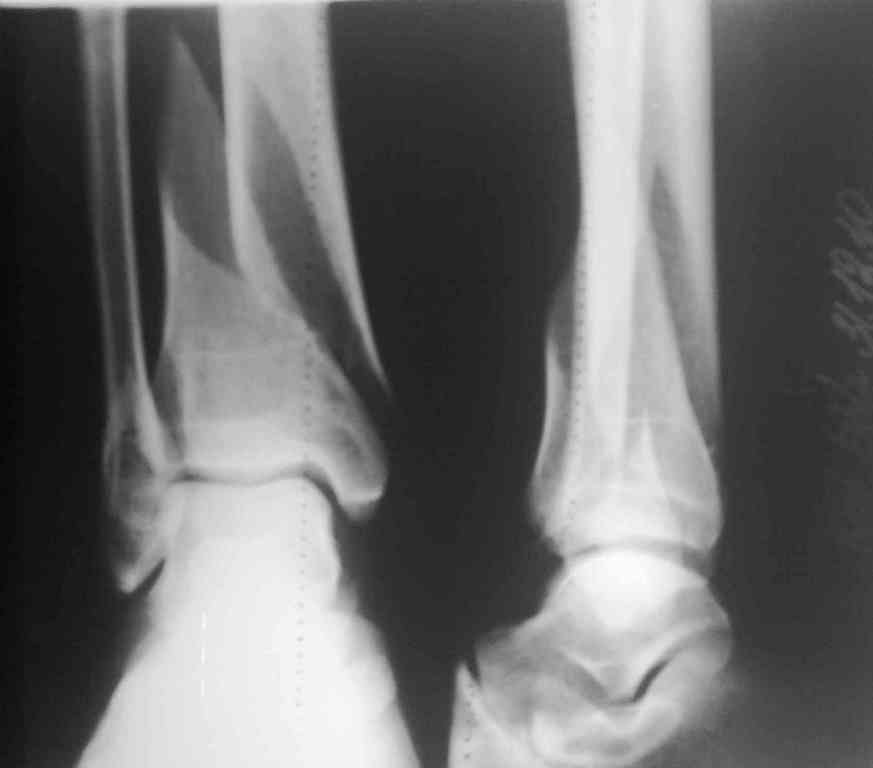

Представляю рентгенограмму перелома обеих костей голени, где определяется разрыв дистального межберцового синдесмоза.

Механизм травмы - подвернул ногу. На боковом снимке видно, что латеральная лодыжка поломана на уровне голеностопного сустава. Во время травмы, кроме воздействия крутящего момента на кости голени, происходило еще и стремительное движение тела больного вниз вместе с проксимальным отломком малоберцовой кости (сила земного притяжения), вследствие чего разрывается межкостная мембрана, передняя межберцовая связка (lig.tibiofibulare anterius), рудиментарная поперечная связка. На боковом снимке конец проксимального отломка ( в данном случае место прикрепления передней межберцовой связки) находится на уровне середины таранной кости. Соответсвенно, последняя разорвана. Смещение отломков костей голени по длине - около 2 см.

Соответственно, из составляющих ДМС осталась целой

лишь задняя межберцовая связка. Хирургу, который будет оперировать пациента, рекомендовано наложить шов передней межберцовой связки, и ввести позиционный винт выше ДМС.